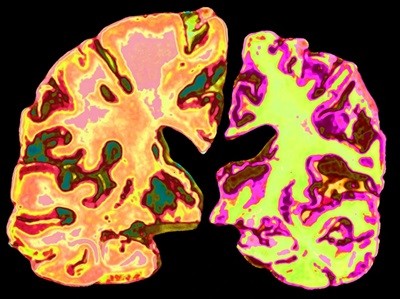

China is waging war on Alzheimer’s. What can its approach teach the rest of the world?

The country is facing a coming wave of dementia for its ageing population, and is investing in research into drugs, diagnostics and even surgery to prepare itself.

Alzheimer’s disease is about to become a big problem for China. Nearly 30% of all people with the condition or related forms of dementia already live in the country. And with its ageing population and falling birth rate, the burden on health and social welfare is expected to multiply dramatically in the coming decades.